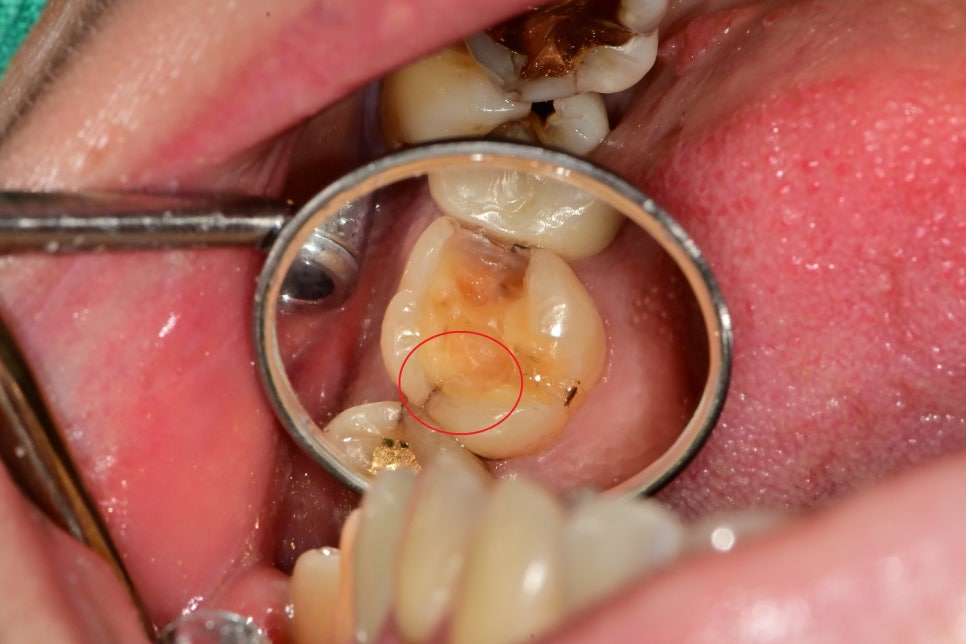

금간 부위와 충치를 제거하는 도중에 안쪽까지 발견된

크랙을 발견할 수 있었습니다.

이런 부분들을 제거하고

임시치아 상태에서도 증상이 나타나지 않아

최종 보철까지 완료할 수 있었습니다.